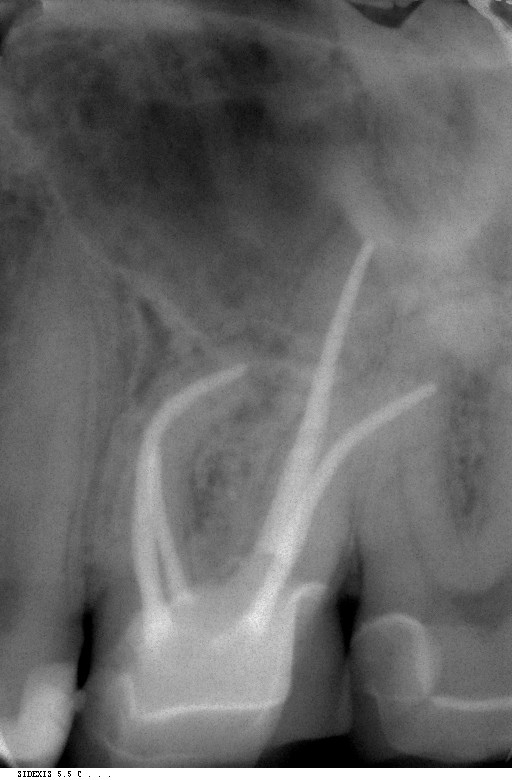

Root Canal Treatment of Tooth in Bridge Dr. Ashish Shah Curved Tooth Root There are a number of methods a clinician might implement to manage curved root canals. Root canal treatment of curved canals presents many challenges for clinicians. If the crown (top) or root of a tooth has an irregular bend, this is known as a tooth dilaceration. It is important to carefully assess the difficulty of cases prior to treatment. These. Curved Tooth Root.